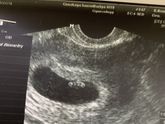

Девочки, к какой недели переставала болеть грудь и заканчивался токсикоз? У меня вот 9 недель, со вчерашнего дня практически даже не тошнит и грудь не болит. На узи была вчера, все в порядке. Малыш растёт